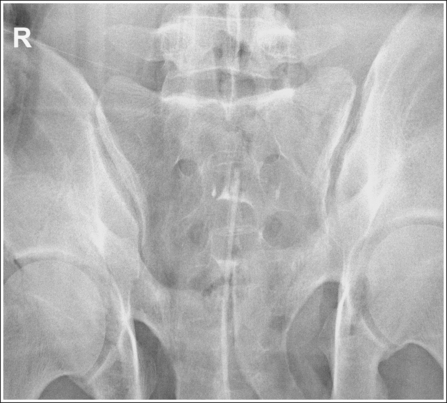

Sacroiliac Joints: Anteroposterior Oblique Projection (Left and Right Posterior Oblique Positions)

See Figure 7-34 and Box 7-8.

A right or left marker identifying the sacroiliac joint positioned farther from the IR is present on the image and is not superimposed over the anatomy of interest.

• Because the sacroiliac joint of interest is situated farther from the IR when AP oblique projections are taken, the marker used should identify the sacroiliac joint situated farther from the IR. This differs from the way most oblique projections are marked; routinely, the side marked is the one positioned closer to the IR.

The ilium and sacrum are demonstrated without superimposition, and the sacroiliac joint is open.

• An AP oblique sacroiliac joint projection is obtained by beginning with the patient positioned supine on the imaging table, with the legs extended. From this position, rotate the patient toward the unaffected side until the midcoronal plane is at a 25- to 30-degree angle with the imaging table and IR. The sacral ala and ilium are positioned in profile. Place a radiolucent support beneath the patient's elevated hip and thorax to help maintain the position (Figure 7-35). Both AP oblique projections (RPO and LPO positions) must be obtained to demonstrate the right and left sacroiliac joints. When AP oblique projections are taken, the elevated sacroiliac joint is the joint of interest.

• Determining accuracy of obliquity. The accuracy of an AP oblique sacroiliac joint projection can be determined by the lack of ilium and sacral superimposition. The degree of separation or cavity demonstrated between the ilium and sacrum, which represents the sacroiliac joint, varies from patient to patient. The ilia and sacrum fit very snugly together and in older patients the joint spaces between them may be smaller or even nonexistent because of fibrous adhesions or synostosis. If the patient was not rotated enough to place the ilium and sacral ala in profile, the inferior and superior sacral aspects of the ala are demonstrated without ilium superimposition, whereas the lateral sacral ala is superimposed over the iliac tuberosity (see Image 25). The lateral sacrum is also demonstrated without ilium superimposition. If the patient was rotated more than needed to position the ilium and sacral ala in profile, the ilium is superimposed over the lateral sacral ala and the inferior sacrum (see Image 26).

The sacroiliac joint of interest is at the center of the exposure field. The sacroiliac joint, sacral ala, and ilium are included within the collimated field.

• Center the central ray 1 inch (2.5 cm) medial to the elevated ASIS to position the sacroiliac joint of interest in the center of the exposure field. Center the IR to the central ray and open the longitudinal collimation to the elevated iliac crest. Transverse collimation should be to the elevated ASIS.